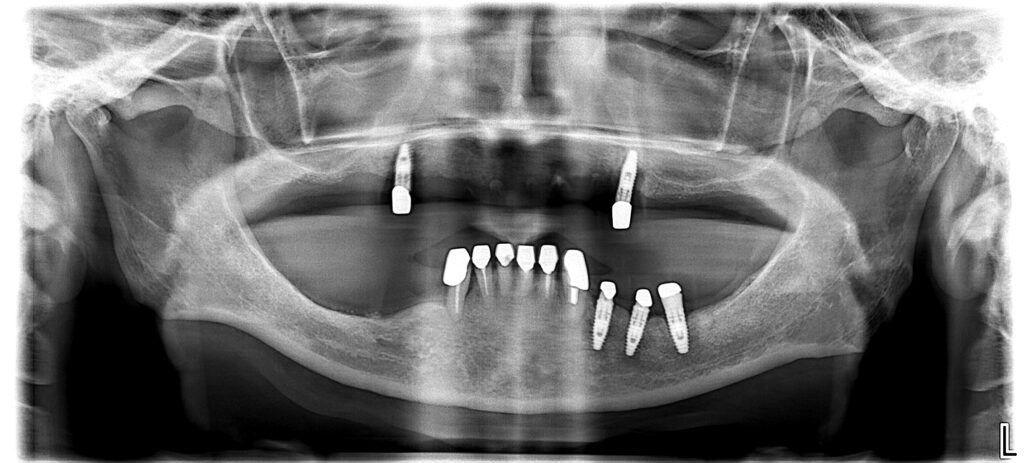

[症例4]

他院にてインプラント治療を行うが、上顎は4本中2本が脱落し、残りの2本のうち1本も膿が出て動揺している。

下顎は右下(向かって左下)3本のインプラントが脱落し、骨の吸収のため最埋入が出来ず、残りの歯を削ってオーバーデンチャー(歯とインプラントの上から被せる義歯)が装着されているが、うまく噛めない上に患者は見た目に不満を持っている。

当院では上顎は前医で埋入した1本のインプラントは保存し、上顎洞に骨を作って新たに3本のインプラントを埋入し、インプラントで支える面積を小さくした総義歯を作成した。

下顎は骨の足りなくなった右下に垂直的に骨を増やし、神経を損傷しないようにインプラントを2本埋入し、左下は古いインプラントを利用して新しいセラミック冠を作成、前歯は歯周治療後にセラミック冠を作成した。

よく噛めるようになり、見た目も審美的になったことで患者は大変満足している。

- 治療期間:2年7カ月

- 治療費:440万円

- 治療回数:50回